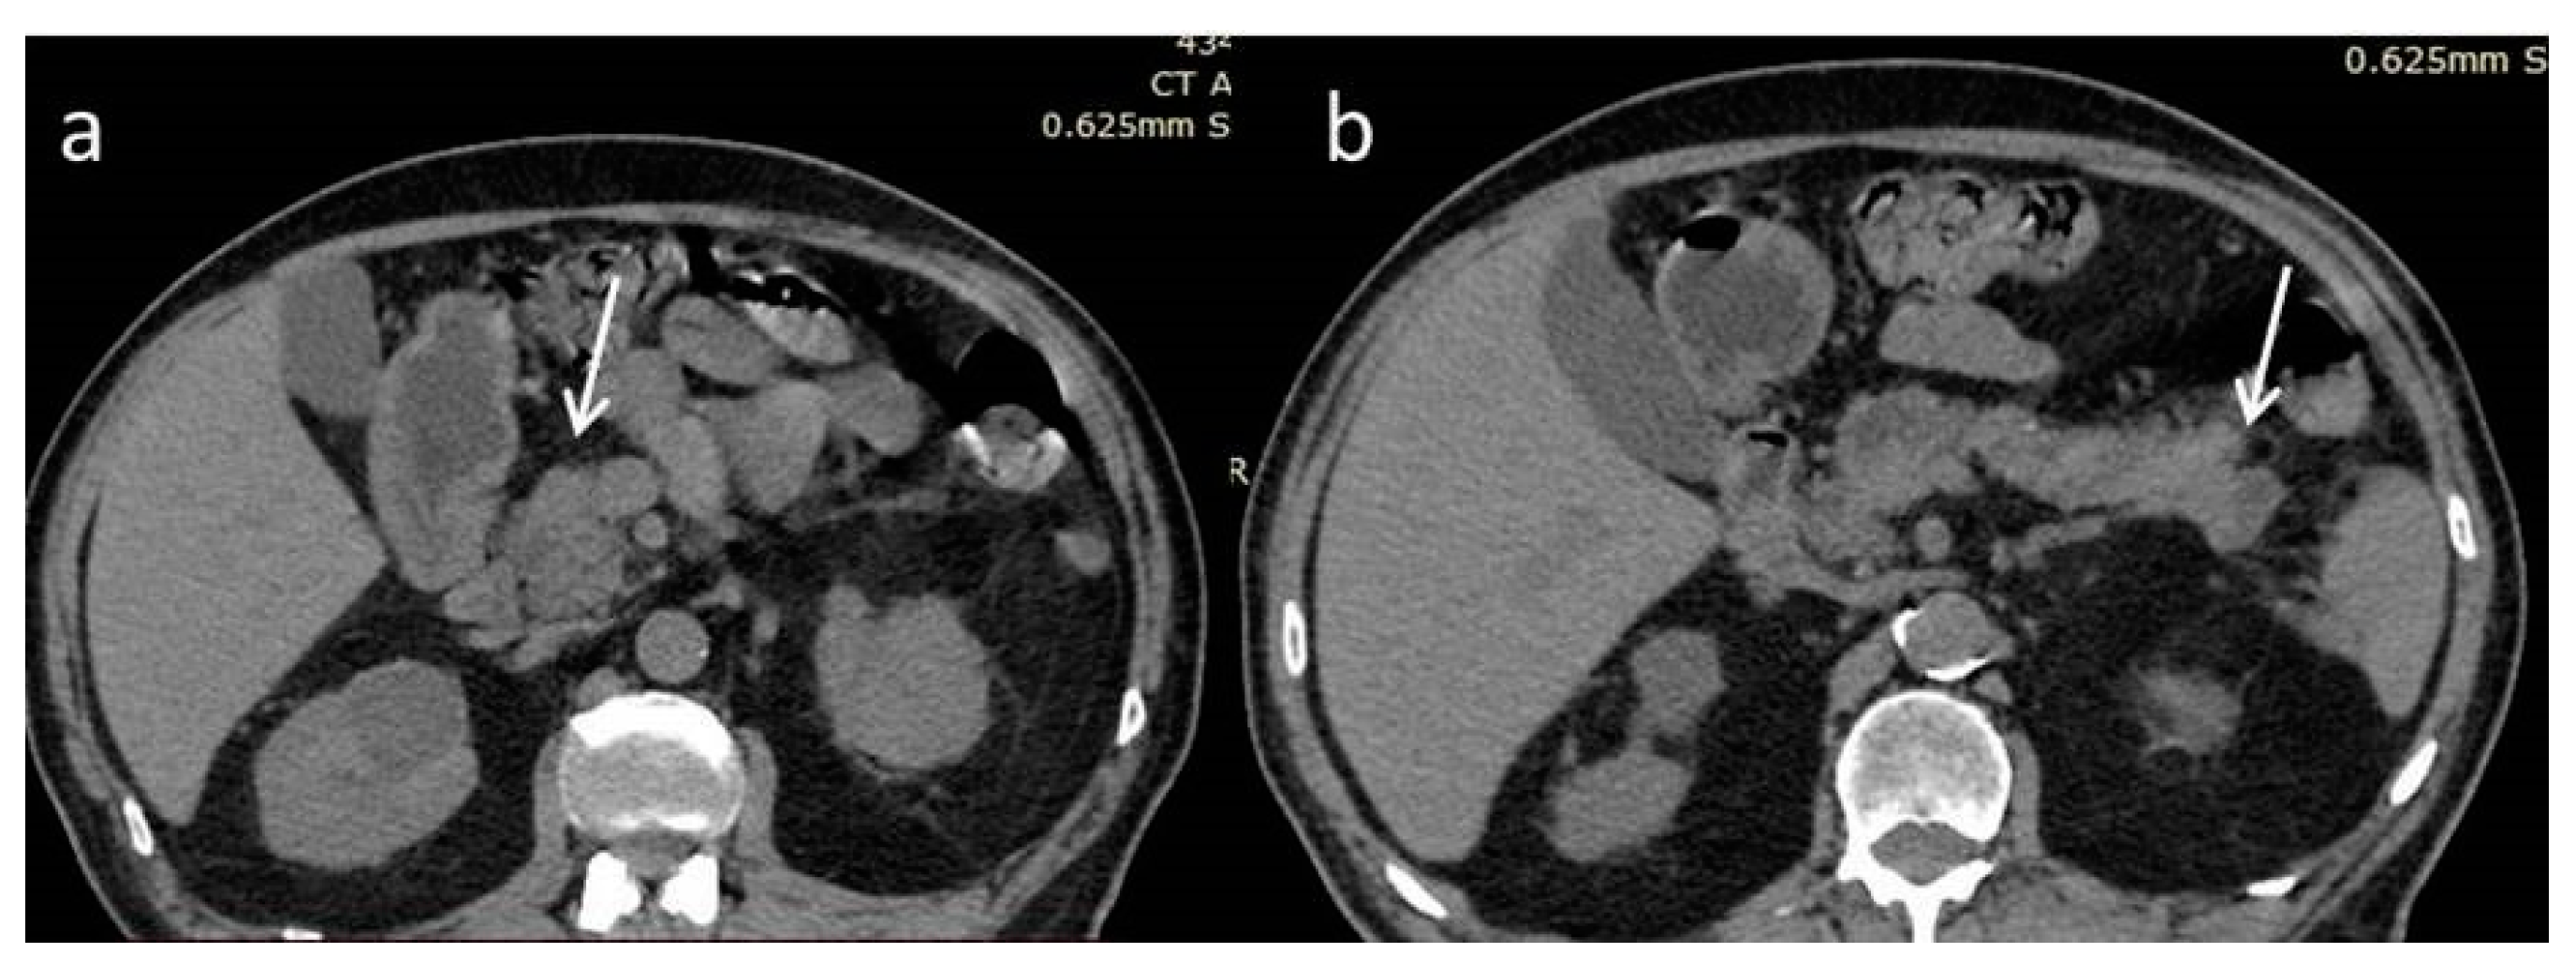

An 80-year-old man was admitted to our department for further investigation and treatment of two pancreatic lesions that were found in an abdominal computed tomography scan (CT) (Figure 1). The patient reported abdominal discomfort and an unexplained weight loss of 15 kg, during the last six months. His medical history includes an appendectomy, pilonidal cyst surgery, a healed gastric ulcer, coronary artery bypass surgery, coronary heart disease, hyperuricemia, hypothyroidism due to de Quervain thyroiditis, hypertension, type 2 diabetes mellitus, and dyslipidemia. He quit smoking thirty years ago, has no history of alcohol abuse, no allergies, and a family history of lung cancer. During the physical examination, there were no abnormal findings.

Figure 1.

Non-enhanced computed tomography scan (NECT). Hypodense, poorly defined masses at the head (a) and tail (b) of the pancreas (white arrows).